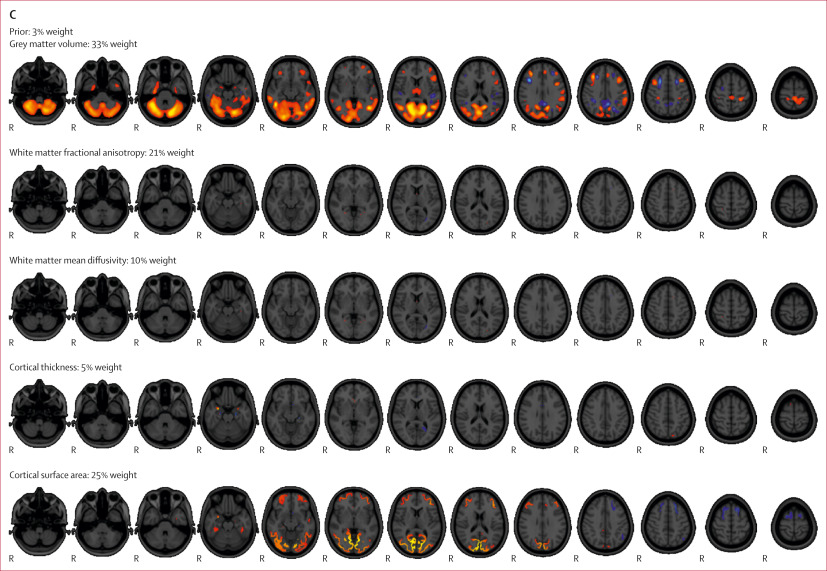

PFAS levels in mothers’ blood associated with children’s brain structure and function

Researchers from the University of Turku and Turku University Hospital, Finland, and Örebro University, Sweden, have discovered that the levels of PFAS in mothers’ blood during pregnancy is associated with their children’s brain structure and Read more